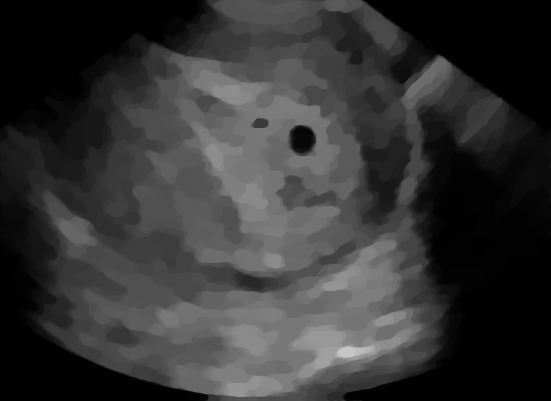

Example 2: restoration of images corrupted by blur and SPN or AWLN. In this example we evaluate the performance of the proposed TV-L1 model on three medical test images lungs (), Fig. 5 (a), ecography (), Fig. 6 (a), and aneurism (), Fig. 7 (a), synthetically corrupted by Gaussian blur of parameters band=5 and sigma=1 and by two types of impulsive noise, namely SPN and AWLN.

| (a) original | (b) TV-L1 (ISNR = 22.13) | (c) zoom of (b) |

![]() |

| (d) corrupted | (e) TVp-L1 (ISNR = 23.15) | (f) zoom of (e) |

| (g) -map () | (h) TV-L1 (ISNR = 25.46) | (i) zoom of (h) |

| (l) -map () | (m) TV-L1 (ISNR = 28.01) | (n) zoom of (m) |

First, for what concerns corruptions by SPN, in Figs. 5, 6, 7 we report for the three considered test images the original and corrupted image together with the estimated -maps in the first column (with the size of the neighborhoods used for the -maps estimation reported in the captions), the restoration results, obtained by the four compared methods, in the second column (with the achieved ISNR values in the captions) and a zoomed detail of the restored images - green- bordered in Figs. 5 (a), 6 (a), 7 (a) - in the last column.

The reported ISNR values as well as the visual inspection of the restored images and of the zoomed details strongly indicate how the proposed space-variant regularizer allows for higher quality restorations. In particular, it is worth remarking how, with respect to the space-variant TV model, the additional degrees of freedom represented by the scale parameters used in our proposal, yield a sufficient additional flexibility for avoiding unwanted spurious effects - see, e.g., spikes in Figs. 5 (i), 6 (i), 7 (i).